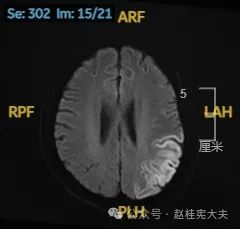

头颅磁共振平扫提示左侧颞枕叶亚急性期脑梗死可能。头颈部CTA示左侧椎动脉颅内段发育不良。头颅磁共振增强+波谱分析提示左侧颞枕叶病灶,考虑脑炎可能大。

入院后给予精氨酸,左卡尼丁,辅酶Q10,维生素E等治疗。患者病情稳定好转中,2天后意识清楚,语言表达仍欠佳。当天复查颅脑磁共振如下:

以上为患者发病后3次的颅脑磁共振片子,临床诊断基本上可以确认了,希望患者逐渐恢复!